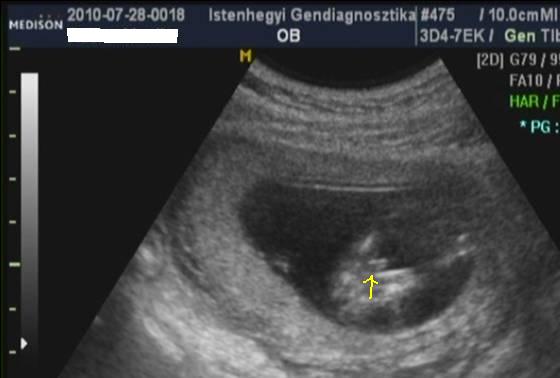

Tényleg csak ezt a 4 hetet kell kivárod és utána már sűrűsödnek az időpontok. Drukkolok hogy rögtön mutassa is meg magát a pindur